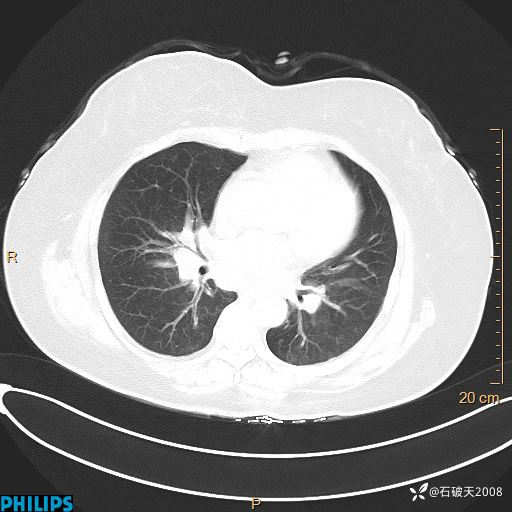

肺结节病?纵膈型肺癌?淋巴瘤?有点意思,欢迎围观

女 52岁 主 诉:咳嗽10余天,咳痰2天。

现病史:10余天前无明显诱因出现咳嗽,呈阵发性干咳,伴咽喉部发痒,无咽痛,无咳痰,无鼻塞、流涕、打喷嚏,无发热、畏寒、寒颤,无头痛、头晕,无胸闷、胸痛,无反酸、烧心,无腹痛、腹泻,无尿频、尿急,无皮疹等,在当地诊所求治,给予口服药物治疗(具体不详),病情无好转。遂在当地社区卫生服务中心开具口服药物治疗(具体不详),疗效欠佳。2天前出现咳痰,在我院门诊求治,行胸部CT提示肺部感染,建议住院,患者要求口服药物治疗,目前仍咳嗽、咳白色粘痰,白天量多,夜间自觉喉部喘鸣音,遂再次来院就诊,以“肺部感染”为诊断收入院。发病以来,神志清,精神可,饮食可,夜间睡眠差,大小便正常,近期体重无明显变化。

肺窗